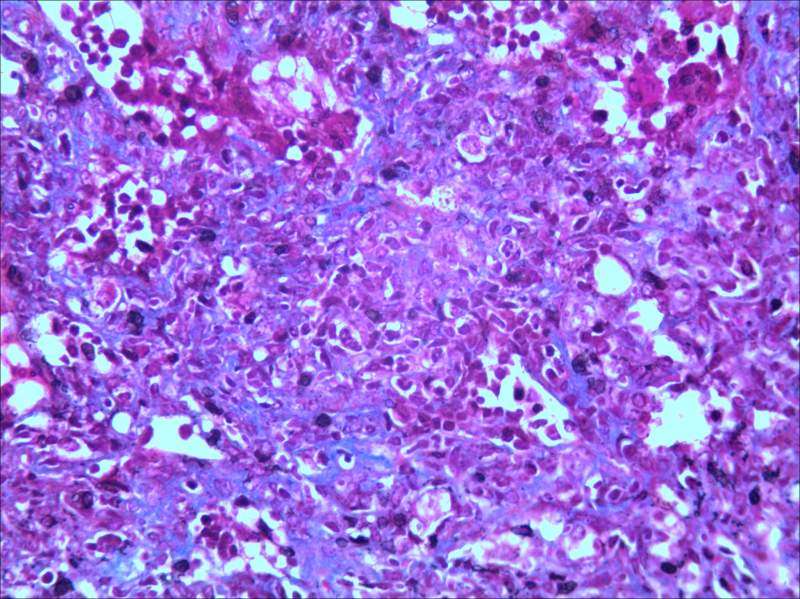

RT£¬ÇóÖú¸ßÈËÖ¸µãÒ»¶þ¡£¡£ÓÃImage J´¦ÀíÂíËÉȾɫÇÐÆ¬Á÷³Ì¡£¡£ ÉÏ´«2ÕÅͼ¡£¡£¡£Çó¾ßÌå½Ì³Ì M10-2-X+++-Y+++.JPG M40-2-X+++-Y+++.JPG |

ÎÒû×ö¹ý£¬µ«ÊǰïÎÒʦ½ã´ò¹ýÏÂÊÖ£¬Ï£Íû¶ÔÄãÓаïÖú°É¡£´ó¸Å²Ù×÷Á÷³ÌÈçÏ 1£®ÍÑÀ¯ £¨1£©½þÅݶþ¼×±½10min£¬½þÅݶþ¼×±½5min£¬½þÅݶþ¼×±½5min£¬½þÅÝ100%¾Æ¾«2min£¬95%¾Æ¾«2min£¬75%¾Æ¾«2min£¬Ë®³åÏ´¸É¾»¡£ 2.Ⱦɫ °ÚºÃƬ×Ó£¬ËÕÄ¾ËØ¼×Òº£ºËÕÄ¾ËØÒÒÒº=1:1Ⱦɫ 5min£¬³åϴȾҺ£¬·ÅÈë¼Ü×Ó£¬Ï¡ÑÎËáպһϣ¬³åÏ´5min£¬°ÚºÃƬ×Ó£¬²Á¸ÉË®£¬¼Ó Àö´ººìËáÐÔÆ·ºìҺȾ7·ÖÖÓ£¬×ÔÀ´Ë®³åÏ´5min£¬ 1%Á×îâËáË®ÈÜÒº´¦ÀíÔ¼5·ÖÖÓ£¬µ¹µôÁ×îâËᣬ²»ÓÃˮϴ£¬Ö±½Ó¼Ó2%±ù´×ËáÊÊÁ¿´¦Àí1·ÖÖÓ£¬×ÔÀ´Ë®³åÏ´5min£¬ÓÃÖÐÐÔÊ÷Ö¬·âƬ¡£ |